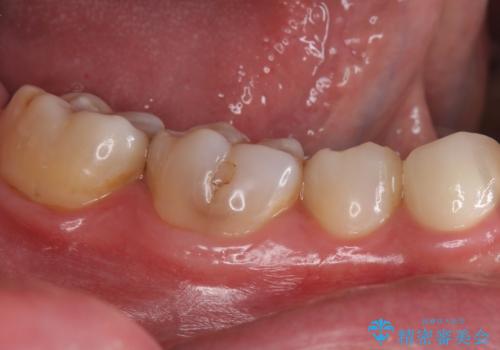

- 右下4 仮歯+ジルコニアクラウン 11000円+110000円費用は治療当時の料金となります

残った歯が薄い状態で保存するとその後の破折リスクが高くなります。

予防的に歯を削りクラウンにすることで治療後の破折リスクを減らすことができます。